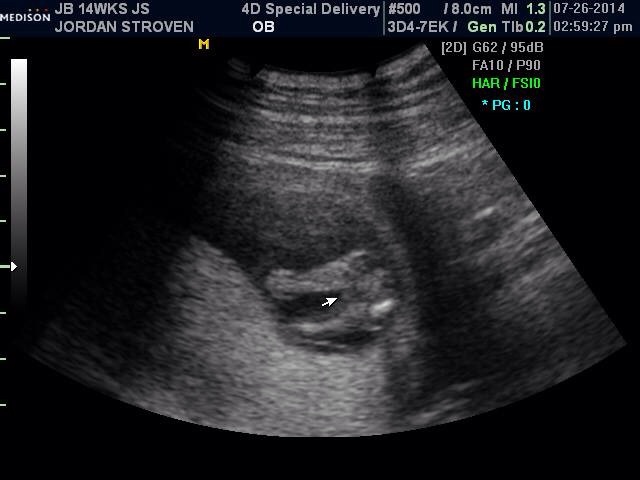

Hi ladies! I just found this site today and I'm so excited and wish I would have found it sooner!! I have a few pictures I'm going to try and upload, one is from my Dr at 12w5d just to show the skull and nub theory, I'm not great about that but just maybe to help. Lol the next is at 13w5d from an elective scan I had to try and see the gender. They leaned towards girl but I'll confirm with my actual Dr sep 5th, it's killing me waiting though! I've had mixed reviews from everyone I've shown! Some say girl, some say boy, some say to keep receipts of I buy pink.... It's so confusing! I wouldn't be so doubtful I think had so many people question the scan, and the fact it took forever to even get a hint! Baby was stubborn! It was supposed to take 15 minutes, took 45.... Two techs.... Me having to get up and move around multiple times. Lol it was a show!

I'm thinking this probably should have been done on my laptop now. I can't organize them very well on my phone, the side view on 2d was at 12w5d everything else like the 3d and between the leg shots were all taken 13w5d I hope that makes sense!